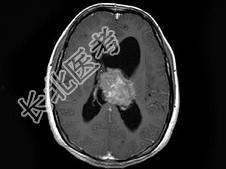

- 单项选择题男,32岁, 头痛呕吐半个月,MRI检查见脑室内占位, 最可能的诊断为 ( )

A、脉络膜丛乳头状瘤

B、室管膜瘤

C、髓母细胞瘤

D、脑膜瘤

E、未见异常